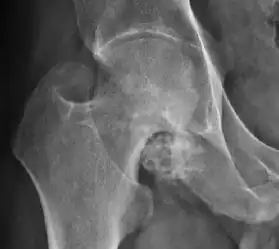

Plain radiography allows us to categorize the hip as normal or dysplastic or with impingement signs (pincer, cam, or a combination of both). Besides these, pathologic processes like osteoarthritis, inflammatory diseases, infection, or tumors can also be identified (Figure 1).[1]

Figure 1.

-

Radiography in normal hip -

X-ray in pincer impingement type of hip dysplasia -

X-ray of cam -

Hip in osteoarthritis -

Septic arthritis